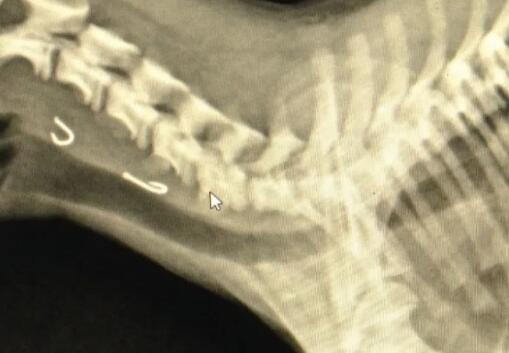

发现狗误食了鱼钩后,刘女士不敢拉扯它,剪下鱼线,然后将狗送至附近的宠物医院。通过拍摄X光片的照片,医生终于找到了鱼钩的位置。X光片显示两个鱼钩在狗的食道上方。